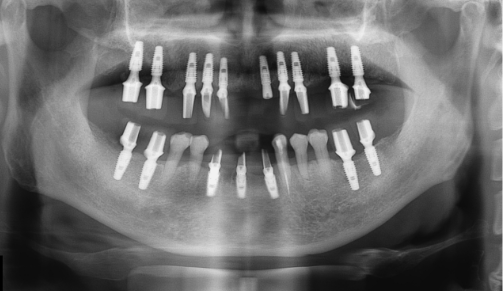

정밀진단

3D 모의 수술을 위해 첨단 장비를 이용하여 환자의 구강 상태, 뼈, 신경의 위치 등의 검사를 진행합니다.임플란트

상실된 치아를 위해 목포미르치과병원에서는 컴퓨터 분석 시스템을 활용하여

개인의 구강 구조를 면밀히 파악하고,

환자의 심미성과 기능성을 모두 만족하는 맞춤형 임플란트를 제공합니다.